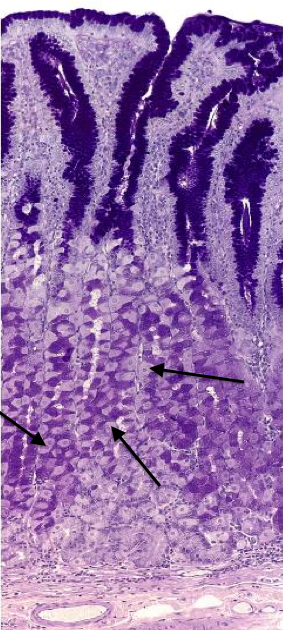

70

Corpora cavernosa

71

Name this tissue

Penis

72

Corpora spongiosum

73